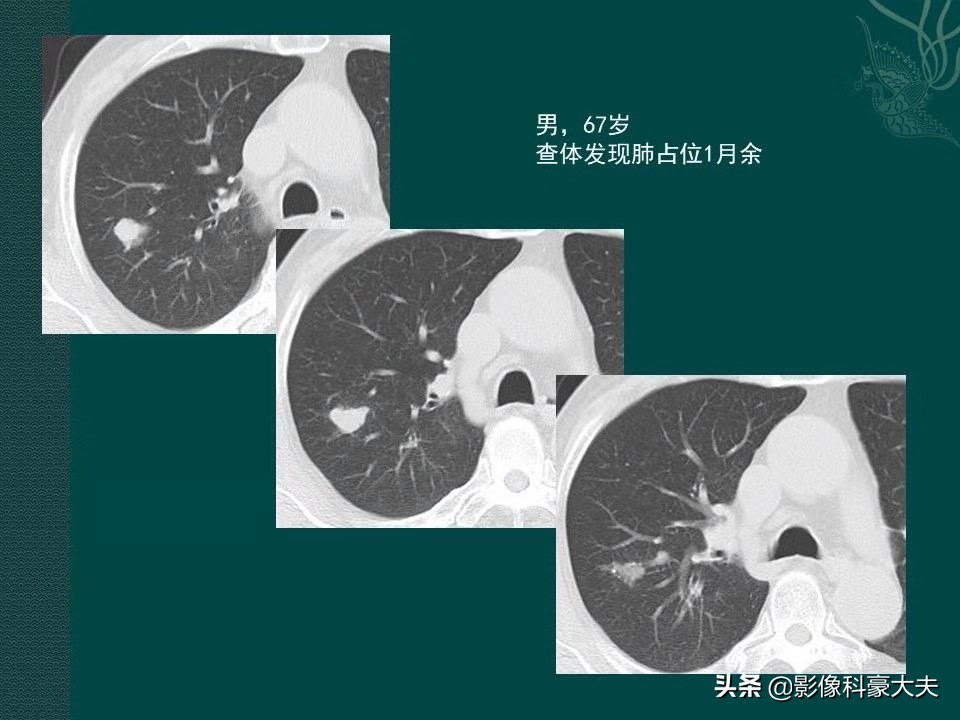

这是一位67岁男性病人,2013年体检发现右肺分叶状实性结节:

本病例来自山东肿瘤医院黄教授

这个病人没有症状,结节比较光滑,会不会是结核球?我们不急于定论,先利用设备的强大后处理功能把图像放大后,观察到两个细节:

肺门侧有一个小结节,首先考虑淋巴结(局部转移),同时结节的远侧带一点光滑的小尾巴,这提示早期转移,淋巴浸润的可能,最符合小细胞肺癌的特点。进一步给病人做了增强扫描,显示这个小结节呈轻度强化(小细胞肺癌大多乏血供,多呈轻度强化),这就不应该直接手术了,需要先穿刺明确病理,因为如果是小细胞肺癌,转移早,进展快,手术不能获益(只有大约5%的局限期小细胞肺癌可以手术)。